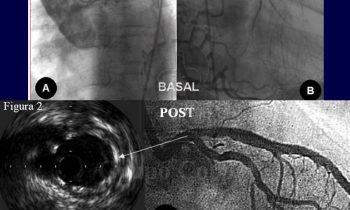

Circulación colateral en la isquemia coronaria aguda

Blog Cardiológico

por Grupo Corpal | 12 Nov, 2021 | Blog Cardiológico, Imagen del mes

Circulación colateral en la isquemia coronaria aguda   Importancia de la circulación colateral en la isquemia coronaria aguda y crónica La circulación coronaria colateral (homo y hetero) puede resultar de una ayuda...

by Grupo Corpal 12 Nov, 2021